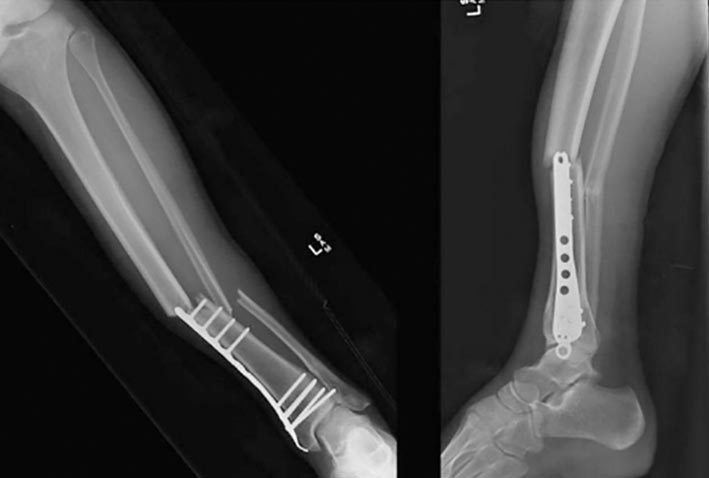

An example is a minimally invasive osteosynthesis (MIPO) by means of a metal plate for iliac fracture newly developed by Ri Thae Hyok, department chief, and Pak Kwang Hyok, Rim Chol Sam and Mun Chang Song, surgeons.

Through years of clinical practice, this procedure has proved effective in minimizing the adverse effects on patients’ health, including less invasion, lower rates of complications such as postoperative infections, and less use of antibiotics. In addition, it minimizes cosmetic injury by surgery.

In addition, medical workers of the department, including Ko Mun Sik and Han Chol Hun, developed highly-effective medical appliances and various advanced surgical methods including LCP-based osteotomy and percutaneous calcaneal tendon closure (PARS) in calcaneal tendon tears.